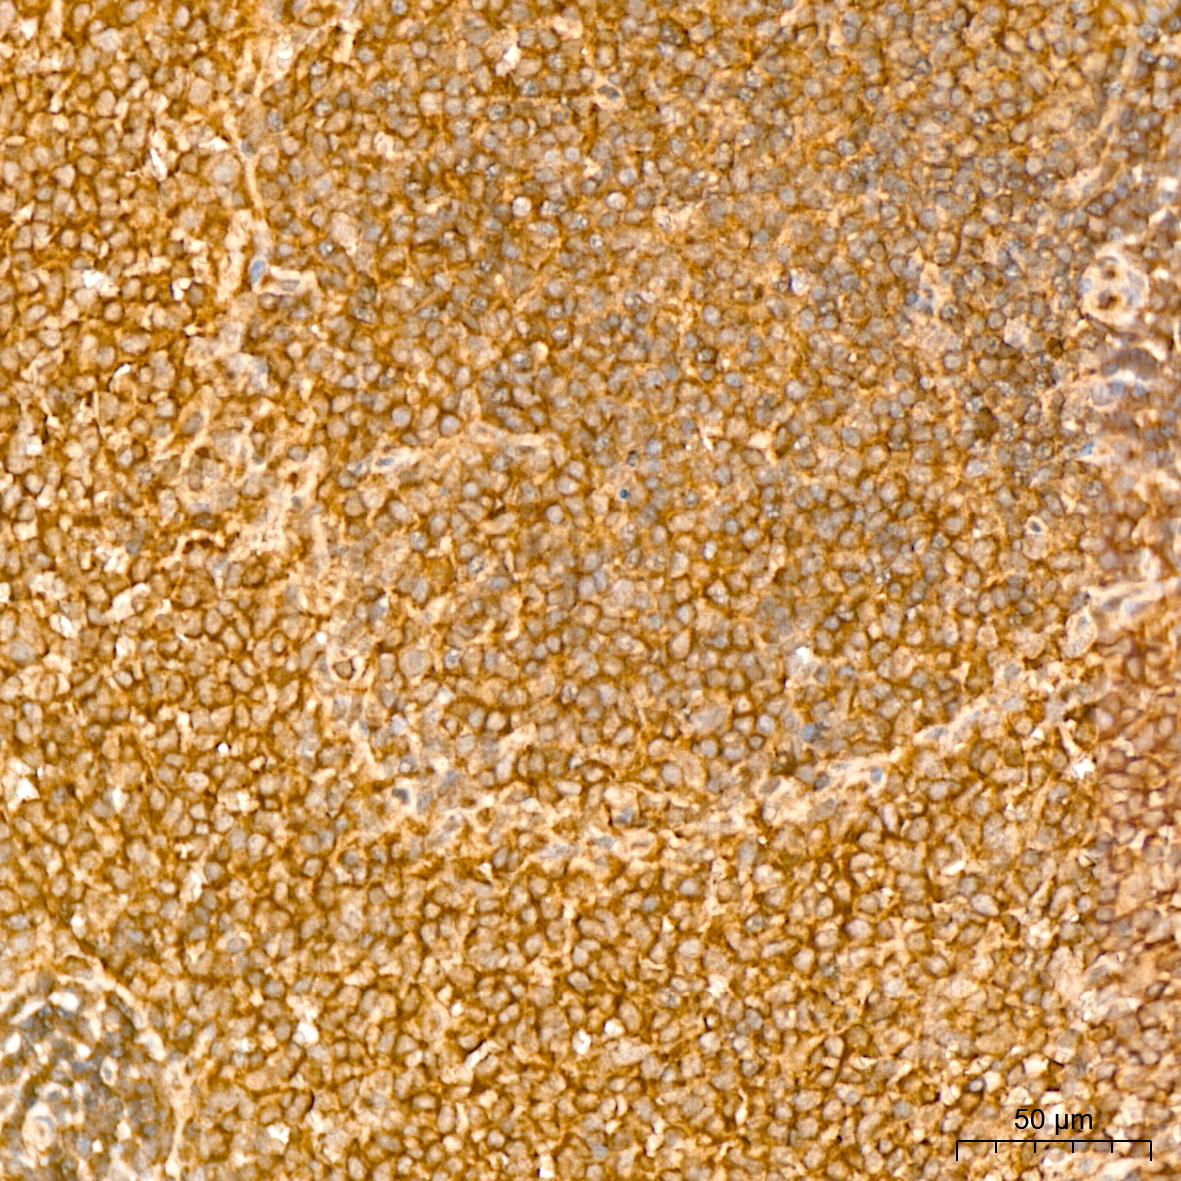

| Immunohistochemistry analysis of paraffin-embedded Rat spleen tissue using NF-kB p65/RelA Rabbit mAb (A19653) at a dilution of 1:800 (40x lens). High pressure antigen retrieval performed with 0.01M Citrate Bufferr (pH 6.0) prior to IHC staining. |